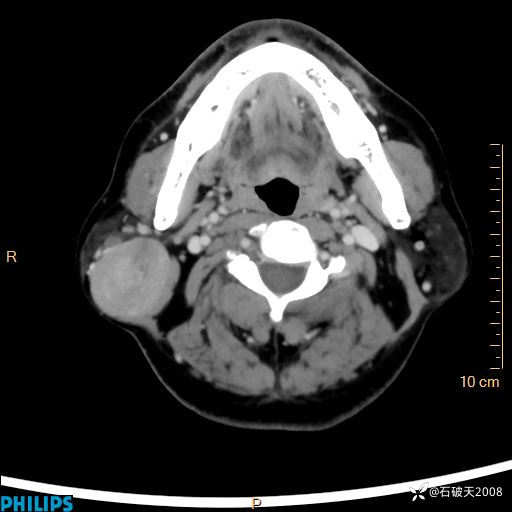

病例分享:颈部占位,一周后公布病理

男 57岁 主 诉:发现右侧颌下肿物1月余。

现病史:1月余前家属发现右侧颌下肿物。局部皮肤无红肿、热痛,无吞咽困难,无异物感,无恶心、呕吐,无头痛、头晕,无胸闷、胸痛,无发热、咳嗽、咳痰及呼吸困难。于我院行体表肿块彩超检查(2024.03.15我院)示:右侧耳下皮下软组织内低回声,未治疗。今为进一步治疗门诊以“腮腺肿瘤”为诊断收住我科,发病来患者神志清,精神可,饮食、睡眠及大小便正常,体重无明显下降。

静脉期